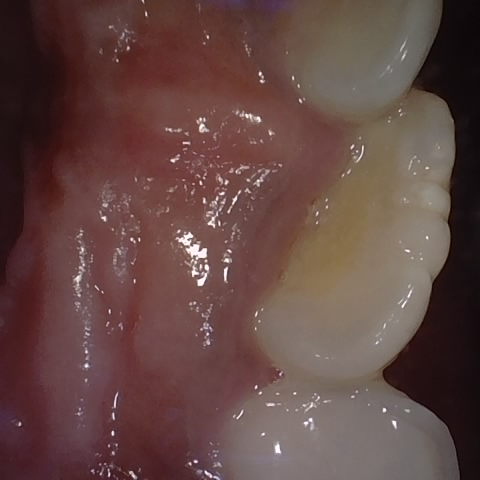

Annotated as "Good"